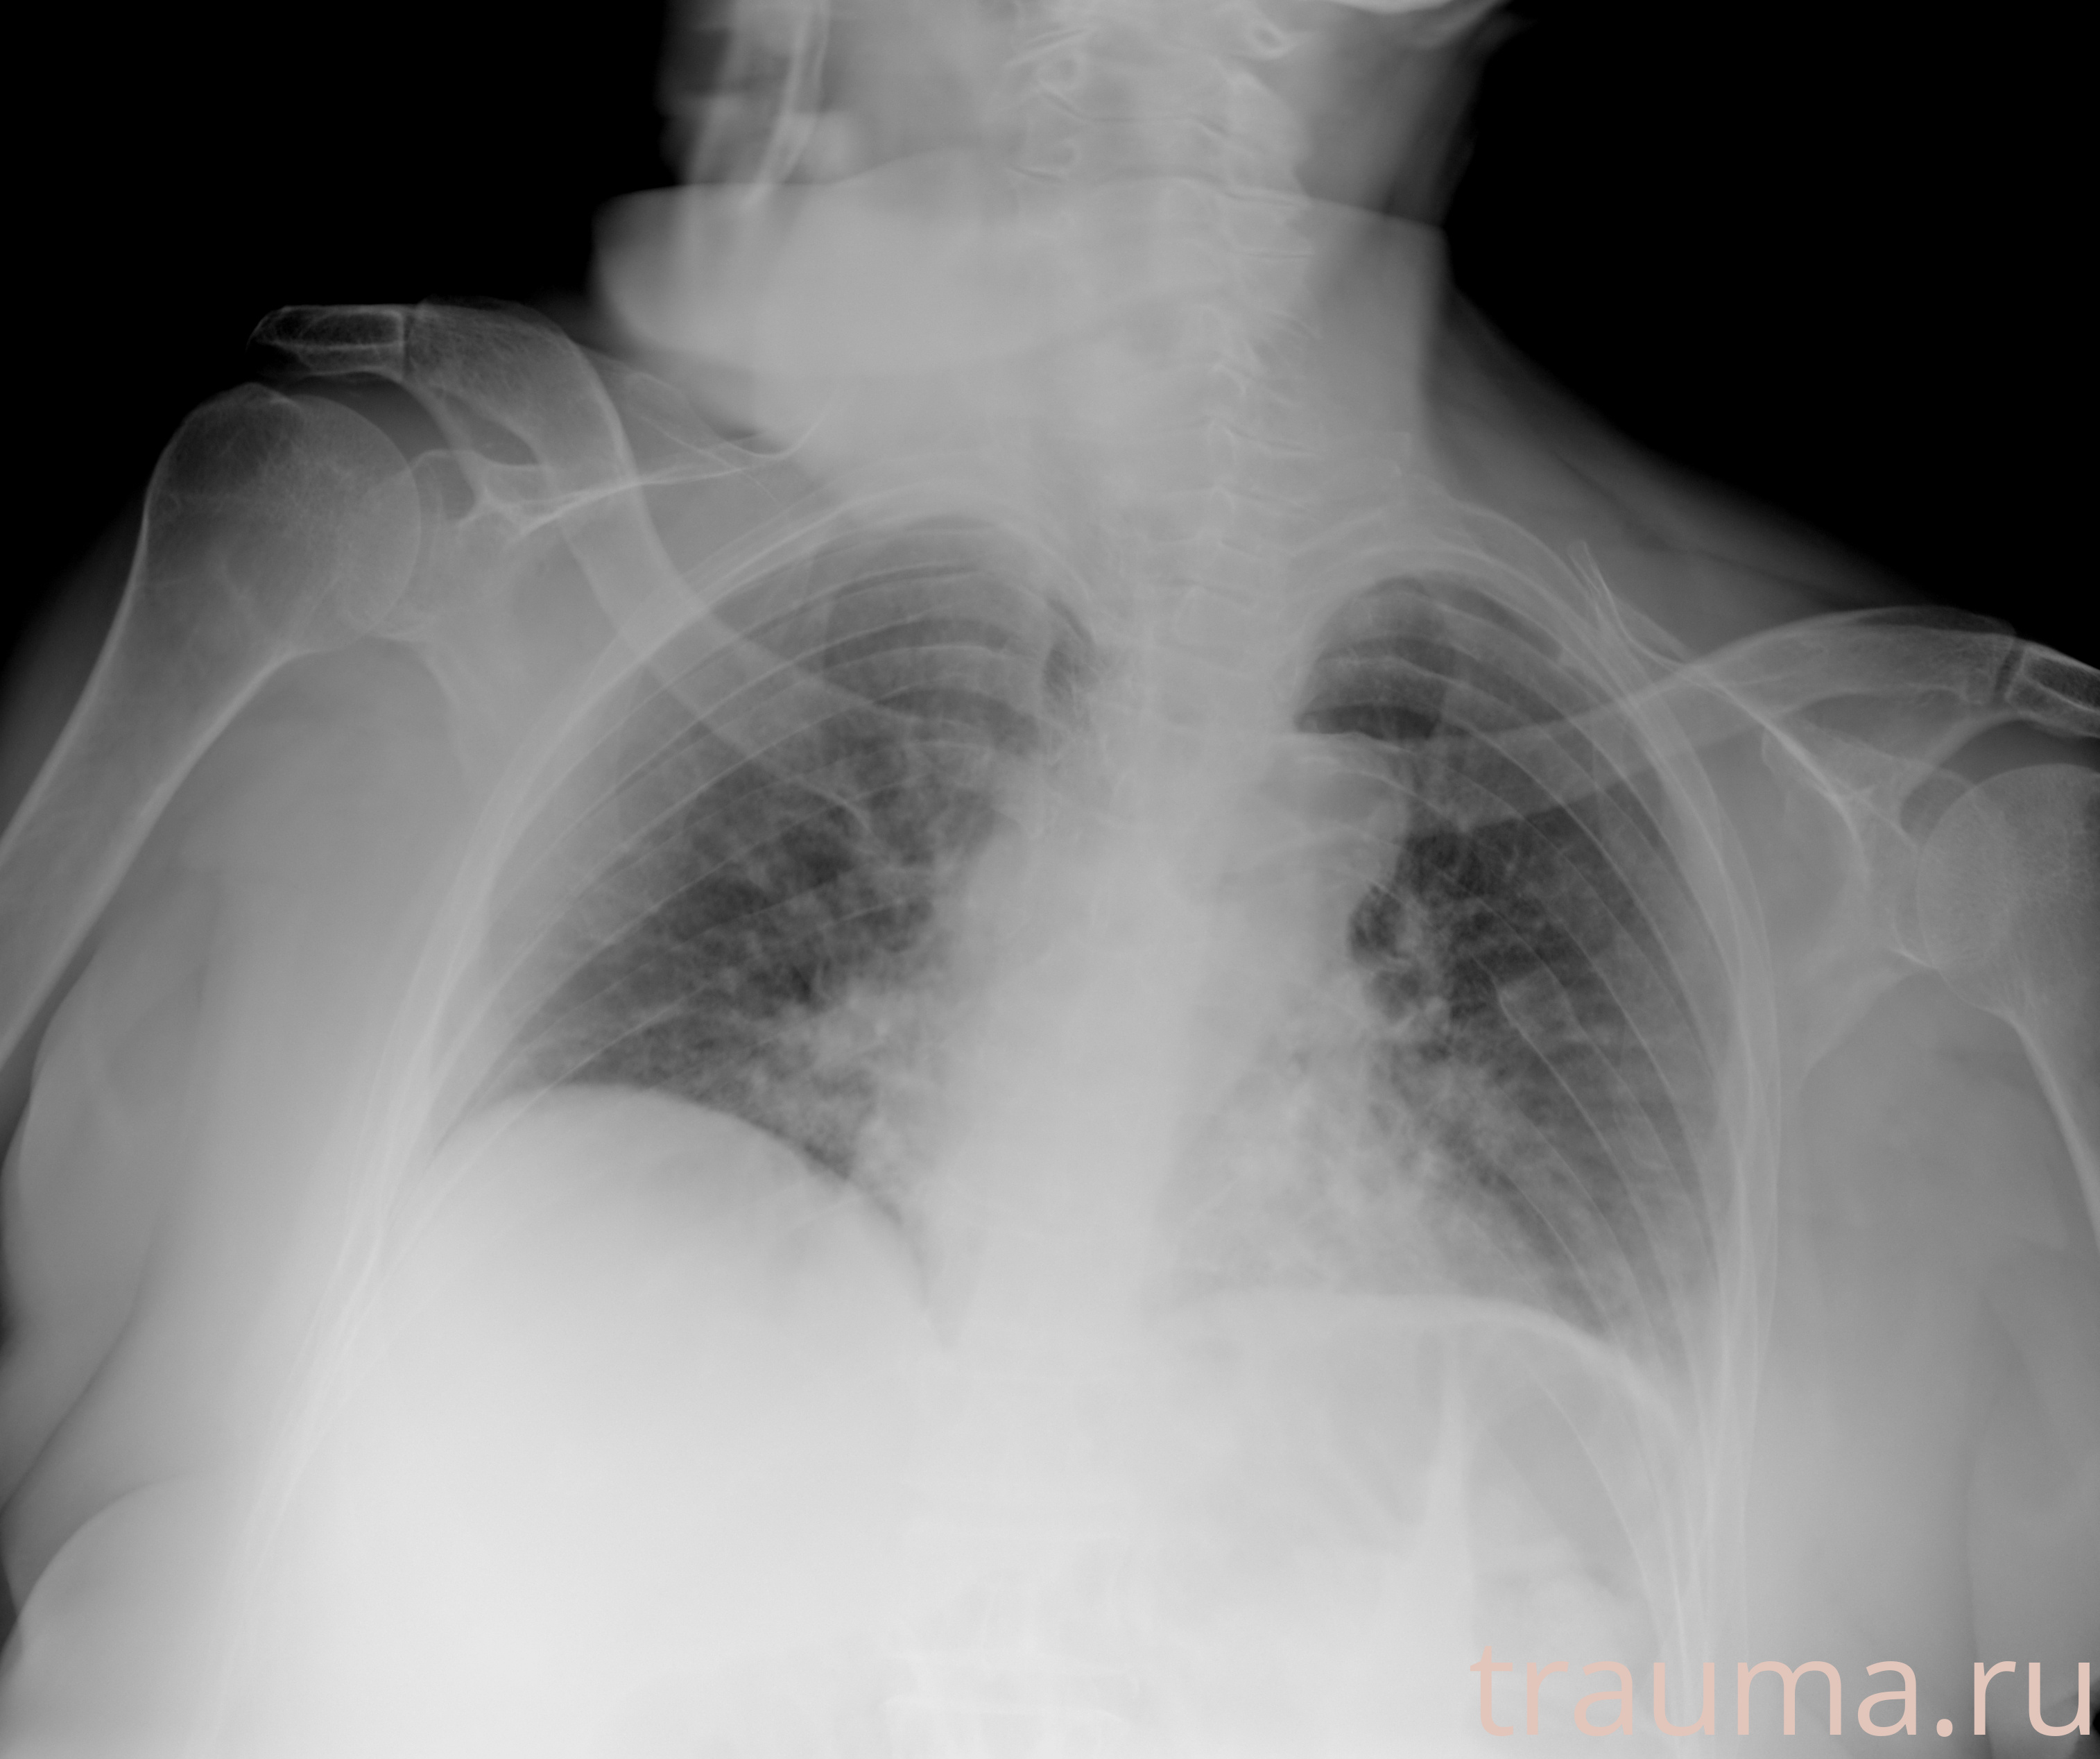

Рентген на дому: по вашему адресу приезжает врач-рентгенолог, травматолог-ортопед с мобильным рентгеновским аппаратом, проводит диагностику травмы или заболевания, делает необходимые рентгенограммы, дает рекомендации по дальнейшему лечению. Получить качественные снимки в домашних условиях возможно благодаря уникальной методике, разработанной МосРентген Центром для института  Склифосовского

при переломе шейки бедра и пневмонии от компании МосРентген Центр - партнера Института имени Склифосовского